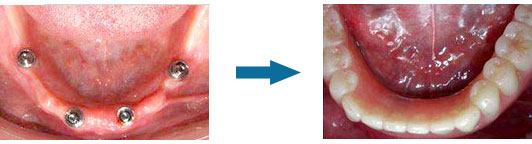

种植医生都知道,单颗种植牙并不难,难的是半口、全口大量缺骨的种植手术。因为全口种植牙涉及复杂的咬合重建,很多牙槽骨缺损严重或高血压、心脏病等疾病患者,找不到种植位点,想种牙都种不了。而康贝佳口腔引进all-on-4即刻种植技术,让半口、全口缺牙,牙槽骨缺损严重,有全身性疾病的患者也能拔牙、种牙、戴牙1天完成了。

1.省事:不用植骨,无需上颌窦提升,手术操作简单化;

2.省时:不用苦熬1年完成修复,拔牙、种牙、戴牙1天完成;

3.省钱:省去价格高昂的骨粉、骨膜费用,仅需4-6颗值体,较传统种植节省1/3费用。